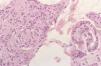

Se realizó biopsia de las lesiones cutáneas (figs. 2 y 3).

Fig. 2.—Estudio histológico: denso infiltrado histiocitario en dermis (hematoxilina-eosina, ×4).

El estudio anatomopatológico mostró la presencia de un denso infiltrado de histiocitos vacuolados desde dermis profunda hasta dermis superficial con una banda subepidérmica respetada, compromiso neural del infiltrado y atrofia epidérmica (figs. 2 y 3). La tinción para bacilos ácido-alcohol resistentes fue claramente positiva (fig. 4).